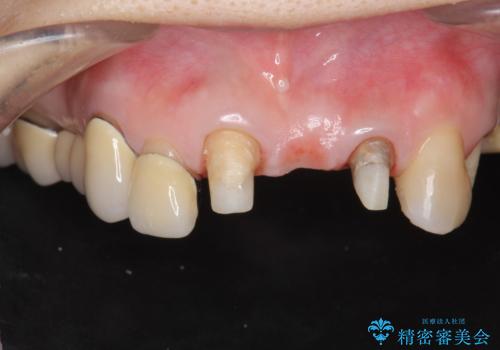

前歯ブリッジのやりかえ

- 前歯の審美障害、見た目の改善を希望され来院されました。

歯肉縁下カリエスも認められるため、挺出を行いセラミックブリッジを審美的に新製します。

- 47万円(仮歯×3・ファイバーコア×2・ジルコニアクラウン×3 歯の挺出)費用は治療当時の料金となります